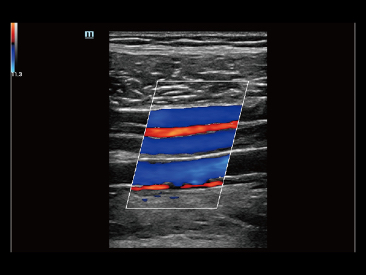

Naast de hoogwaardige beeldvormingskwaliteit verbetert de Resona 7 tevens de klinische onderzoeksmogelijkheden met de revolutionaire V Flow voor vasculaire hemodynamische evaluatie, en de intelligentste vlakacquisitie van een 3D-gegevenssets voor de diagnose van het foetale, centrale zenuwstelsel. Met zijn combinatie van de meest intu?tieve, op vingerbewegingen gebaseerde multi-aanrakingsbediening en alle essenti?le klinische functies loopt de Resona 7 voorop in de nieuwe golven van ultrasoundinnovatie.